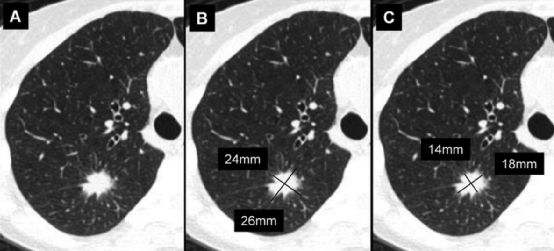

右肺上叶磨玻璃结节 (箭头) 的时间顺序扫描。结节的平均直径为A、13mm,B、14mm,C、18mm。当我们将最早的图像与最新的图像进行随访,测量应在结节中心层面上进行,不一定和上次检查的解剖学层面相同。